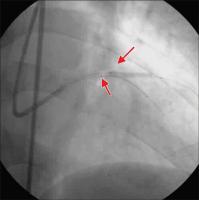

Sondierung - BMW-Führungsdraht

Abbildung 3: Sondierung beider Ästen mit je einem BMW-Führungsdraht (Guidant). Vordilatation des Ramus diagonalis mit einem 2,5 / 20 mm-Ballon (Hypro Pegaso, Sorin Biomedica) - 16 atm.

Keywords: KardiologieKoronarangiographieRamus diagonalis